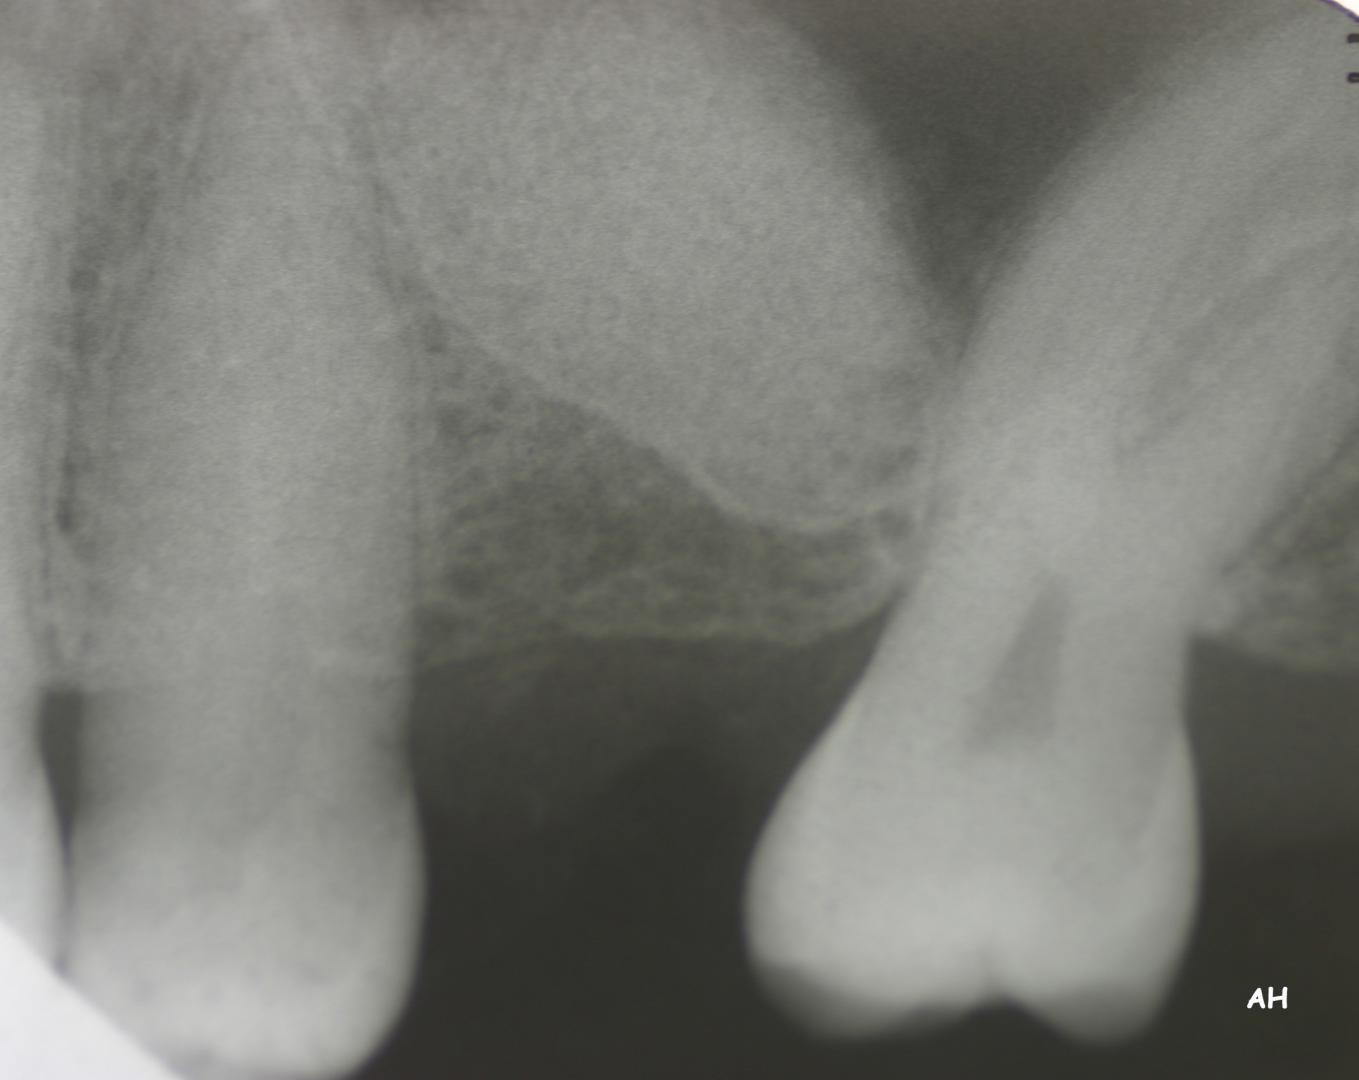

Exemple 14: Il est prévu de mettre un implant entre la molaire et prémolaire, mais le sinus se trouve à moins de 4 mm de la surface. Il faut donc relever le sinus avec une greffe d'os

Exemple 14: Un petit puits d'accès est créé afin d'atteindre le sinus, notez la membrane sinusienne.

Exemple 14: La fine membrane sinusienne est relevée, puis de l'os mélangé à de l'os artificiel est introduit dans la cavité.

Exemple 14: La cavité est maintenant remplie.

Exemple 14: Radiographie post chirurgicale.

Exemple 14: 6 mois plus tard, l'implant est introduit dans cette greffe sans toucher le sinus.